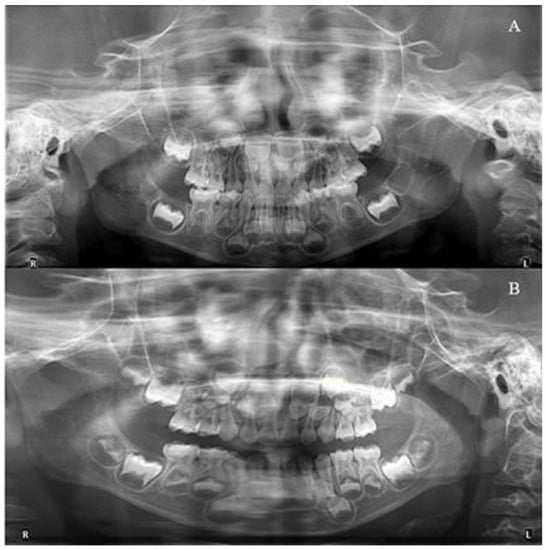

The patient and his parents allowed the use of his medical records, photographs and radiographs in this research. Prior to the initiation of therapy, panoramic and lateral cephalometric films were obtained. The panoramic radiograph showed swelling in the bilateral nasal mucosa (Figure 4). A mild skeletal Class II sagittal relationship (ANB = 5.4°) and large mandibular plane angle (SN-MP = 39.8°) were indicated in the pre-treatment cephalometric film (Table 1). Meanwhile, his hyoid (MP-H) rested lower than normal (16.8 mm, mean normal = 14.2). In addition, he had a hyperdivergent growth pattern (facial height index, S-Go/N-Me = 57.9%). The airway width assessment showed that he had a limited nasopharyngeal airway gap and expanded oropharyngeal segments (data shown in Table 1). His adenoids were diagnosed with moderate hypertrophy (Figure 5) with an A/N of 64.5% [11,12], which was derived from an adenoidal–nasopharyngeal ratio (AN ratio) via linear measurements using lateral radiographs of the nasopharynx according to Fujioka et al. and Zou. et al. [11,12]. Considering that adenoids in children are physiologically enlarged between 2 and 12 years of age, Zou proposed that an A/N ratio of 0.60 should be considered as normal; 0.61–0.70 is considered as moderate hypertrophy; ≥0.71 is considered as pathological hypertrophy [12]. The digital models’ STL files were uploaded to the Geomagic Studio 12.0 software (Research Triangle Park, NC, USA) for measurement (Figure 6 and Figure 7). The statistics concerning the widths of the dental arch and basal skeletal, as well as the height, surface area and volume of the palatal, are displayed in Table 2.

Furthermore, during orthodontic treatment, his parents visited the ENT department for the hoarseness of the boy’s vocal cords. Rhinoscopic examination revealed enlarged adenoids that blocked 1/4 of the posterior nostril and bilateral vocal fold nodules. The boy was also diagnosed with second-degree tonsillar hypertrophy, variable rhinitis and chronic sinusitis (schematic in Figure 12; the whole timeline of disease history in Figure 13). The otolaryngologist prescribed nasal drops for rhinitis and suggested a follow-up for other diseases, including tonsillar and adenoids. After treatment, the bilateral nasal mucosa swelling was alleviated, as indicated in Figure 3. Moreover, the intraoperative posteroanterior cephalograms revealed a mild flexion of the cervical spinous process, which required observation and follow-up according to a spine surgeon (Figure 14). The therapy duration was seven months, after which all the chief complaints were resolved (Figure 15 and Figure 16).

Figure 4. The initial and final radiographs. (A): Pre-treatment; (B): Post-treatment.